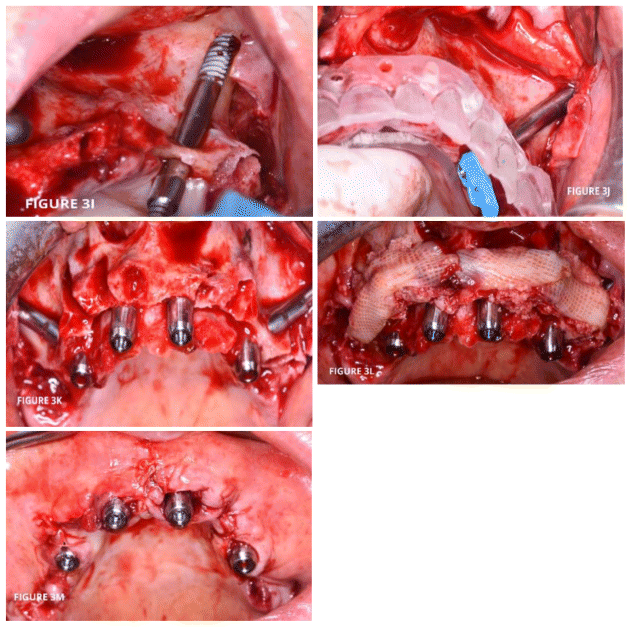

The surgical procedure was then carried out (Figure 3). The intervention was performed under general anesthesia, following an anesthesiological consultation and preoperative examinations.

Following the extraction of the residual dental elements, a full-thickness mucoperiosteal flap was raised, paramarginal in the palatal direction, from the midline to the area ideally occupied in the arch by the second molar, with a vertical posterior releasing incision at the level of the retromolar trigone.

The flap was carefully dissected both at the vestibular level and at the level of the palatal fibromucosa for its entire length. The flap was released buccally to allow skeletonization of the maxillary bone. The exposure of the anterolateral face of the maxillary bone allowed the identification of the nasal fossae, skeletonizing the piriform aperture to mobilize the flap, and the infraorbital foramen with the emergence of the homonymous nerve. In the buccal dissection phase, the zygomatic process of the maxillary bone was then reached, highlighting the body of the zygomatic bone and exposing its temporal portion. The zygomatic arch was skeletonized in the coronal, caudal, and posterior directions to highlight the zygomatic knob, and the anterior zygomatic insertion of the masseter muscle was identified and sectioned, allowing control of the entire zygomatic body. The emergence of the infraorbital nerve was highlighted with a dermographic pencil, drawing a horizontal line above the homonymous foramen, which was then directed towards the zygomatic knob. This delineated the safety area within which the surgeon could operate, avoiding complications secondary to orbital involvement.

Subsequently, a preliminary phase of surgical site preparation was performed using a bur or bone rongeur to level the residual alveolar bone and obtain a bone plateau.

The use of a bone-supported surgical guide, constructed from the stereolithographic model, allowed the preparation to be oriented by tracing the implant preparation trajectory with a dermographic pencil.

The preparation of the surgical site began with the execution of the osteotomy on the anterolateral wall of the maxillary bone, on the plane that ideally connects the buccal region of the residual bone crest to the zygomatic knob. Using a traditional bur on an implant motor, a groove was then prepared on the anterolateral wall of the maxilla, delineating the extra-sinus preparation path, in which the body of the implant would be placed without invading the maxillary sinus, ensuring that the Schneiderian membrane remained intact.

The preparation of the residual alveolar ridge was then continued using the piezoelectric motor, maintaining the bone bridge at the crest level.

Finally, following the previously created groove, the cortical bone of the zygomatic knob was prepared, maintaining the angulation provided by the previous preparatory phases. At this point, the zygomatic bone was prepared using appropriate ultrasonic inserts combined with traditional burs on an implant motor, with the bur in the previously prepared site, and then proceeding with spiral rotating burs.

The implant length was confirmed by measuring the preparation depth with a millimeter probe.

The next phase involved inserting the implant using an implant motor with a minimum torque of 35 Ncm, ensuring favorable crestal emergence for access to the prosthetic abutment. The implant tightening torque of at least 35 Ncm allowed the insertion of the MUAs at 60°, which were then tightened and protected by a healing cap for immediate loading.

In each hemiarch, a zygomatic implant measuring 3.5 mm in diameter and 42.5 mm in length was inserted, along with a paranasal implant measuring 3.3 mm in diameter and 13 mm in length.

After completing the right hemiarch, the procedure continued on the left hemiarch, performing the same surgical procedures.

Following implant placement, a regenerative procedure with CGF was performed.

The procedure ended with suturing the flap with interrupted sutures using 3/0 Vicryl resorbable thread, and attention to the initial incision ensured an adequate band of attached gingiva around the abutments.